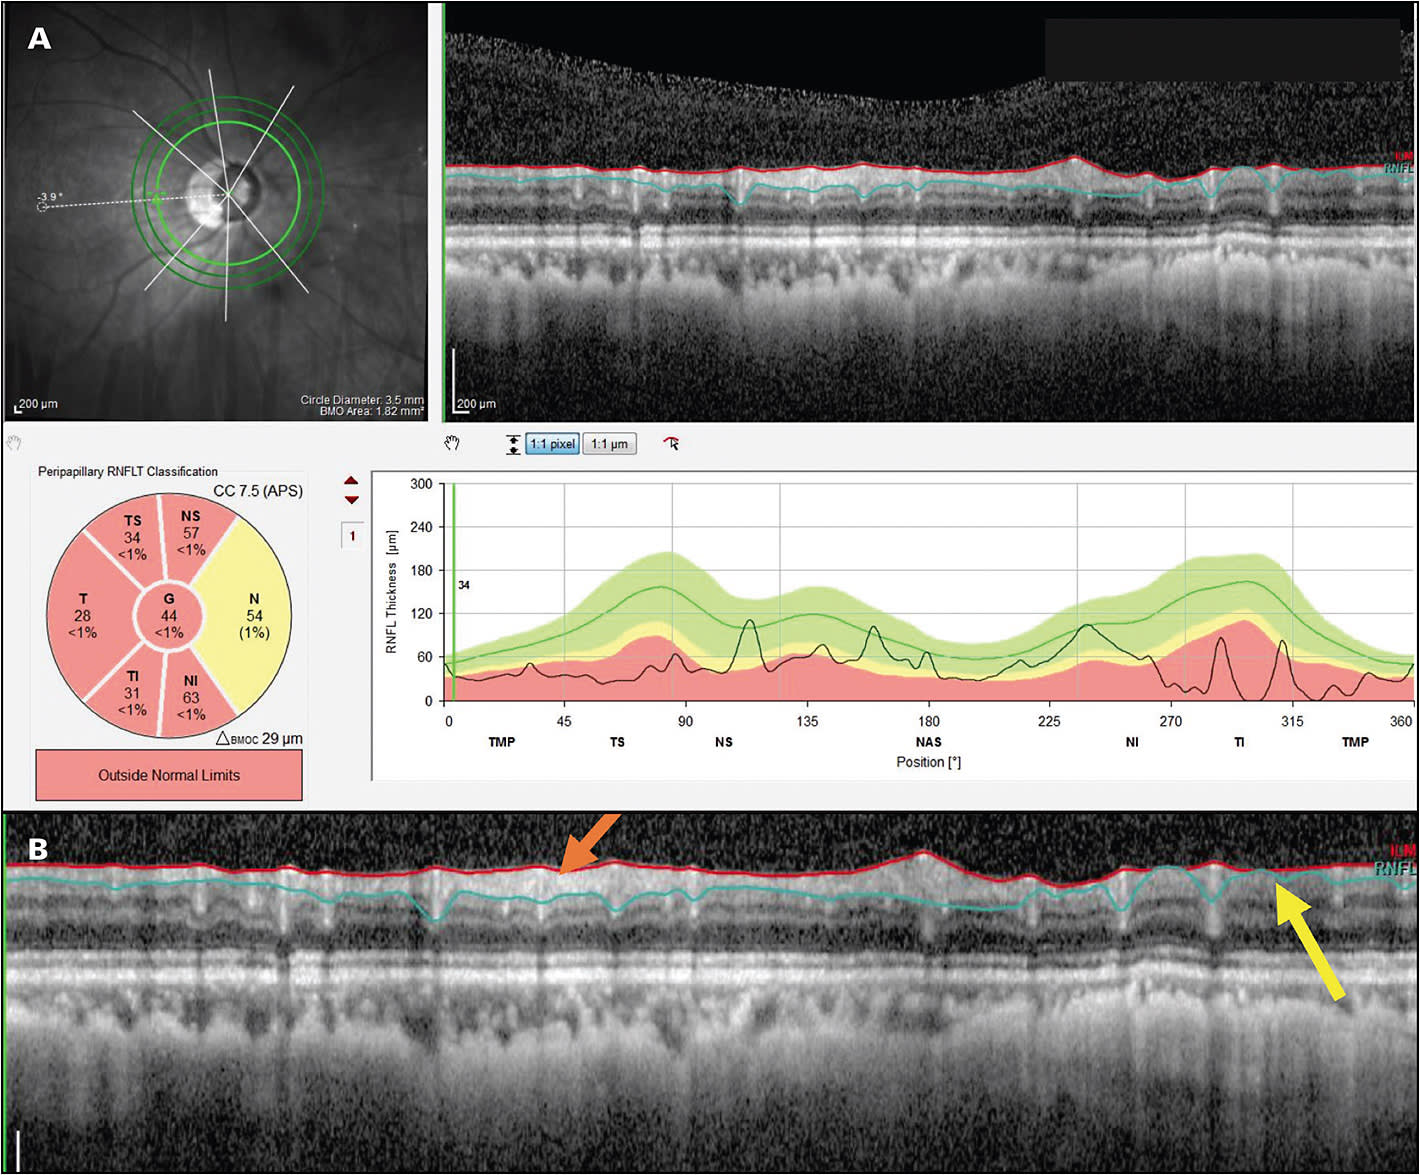

A: Yes. A common assumption is that you can’t test individuals with high myopia with OCT because the standard summary statistics used for OCT interpretation are based on norms from individuals who don’t have high myopia. However, while it is true that the summary statistics cannot be trusted in such cases, it is possible to evaluate glaucomatous damage in many high myopes. The key is looking at the B-scan image around the disc, the so-called circumpapillary retinal nerve fiber (RNFL) image. In most eyes with high myopia, it is relatively easy to identify glaucomatous damage. A study we published recently looked at 100 high myopes to determine whether glaucomatous damage can be accurately diagnosed in high myopes by assessing OCT results. In 97 of 100, we were able to correctly determine if the eye was healthy or glaucomatous based on the OCT image, without making use of the summary statistics.3

A: All of the available OCT platforms offer reports. Every OCT scan of the disc has a B-scan image showing the RNFL around that disc. You want to look at this image (Figure 1). While you may not be able to trust the summary statistics, such as global thickness, you can see local damage on the image, as well as the regions with and without RNFL tissue remaining (Figure 1B). Another important concept is the deviation or probability maps. All OCT instruments now have a deviation or probability map that shows where the RNFL is abnormal and where the ganglion cells are abnormal. In many patients, even high myopes, these can be useful. Some patients have other kinds of problems, for example, peripapillary atrophy, that is so bad that it makes OCT difficult to use even with B-scan images and probability maps. So it’s not for all patients, but for many, if not most, high myopes, OCT will be useful.